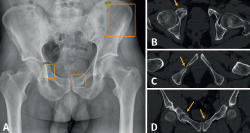

retla.08115.fs2402001-figura5.png

Figura 5. Paciente politraumatizado con múltiples fracturas en el anillo pélvico: radiografía (Rx) anteroposterior de pelvis (A) y tomografía axial computarizada (TAC) con imágenes axiales (B y C) y coronal (D). La inteligencia artificial (IA) señala 3 fracturas en la Rx de pelvis (A). La TAC confirma 2 de ellas en ambas ramas iliopubianas (B y C), pero no detecta la de pala ilíaca. Sin embargo, la TAC detecta otra fractura en la rama isquiopubiana derecha (C), no detectada por la IA.

Figura 5. Paciente politraumatizado con múltiples fracturas en el anillo pélvico: radiografía (Rx) anteroposterior de pelvis (A) y tomografía axial computarizada (TAC) con imágenes axiales (B y C) y coronal (D). La inteligencia artificial (IA) señala 3 fracturas en la Rx de pelvis (A). La TAC confirma 2 de ellas en ambas ramas iliopubianas (B y C), pero no detecta la de pala ilíaca. Sin embargo, la TAC detecta otra fractura en la rama isquiopubiana derecha (C), no detectada por la IA.